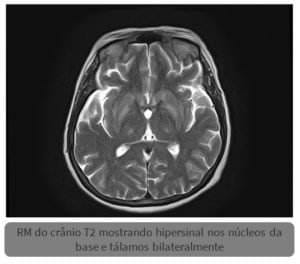

Sinal do tridente na síndrome da desmielinização osmótica